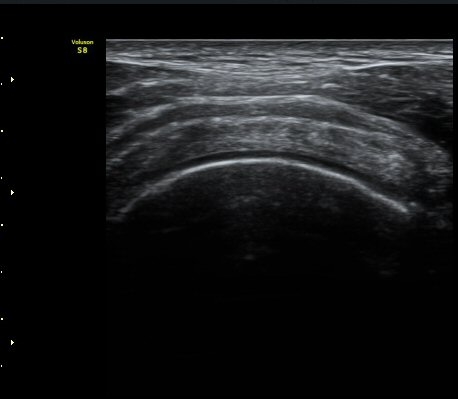

±Ø»ó°Ç ¿øÀ§ºÎ Ⱦ´Ü¸é°Ë»ç¿¡¼­ ´ë°áÀý°ú »ó¿Ï°ñµÎ ÀÌÇàºÎÀ§¿¡ ÇÇÁú°ñ ¿¬¼Ó¼º ¼Ò½ÇÀ» º¸ÀÓ(±×¸² 7).